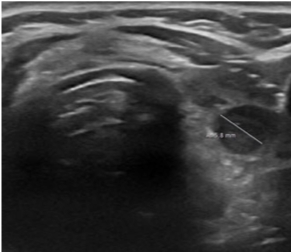

Фотографии и снимки – УЗИ узл

щитовидной железы до проведения

термоабляции и через 6 месяцев